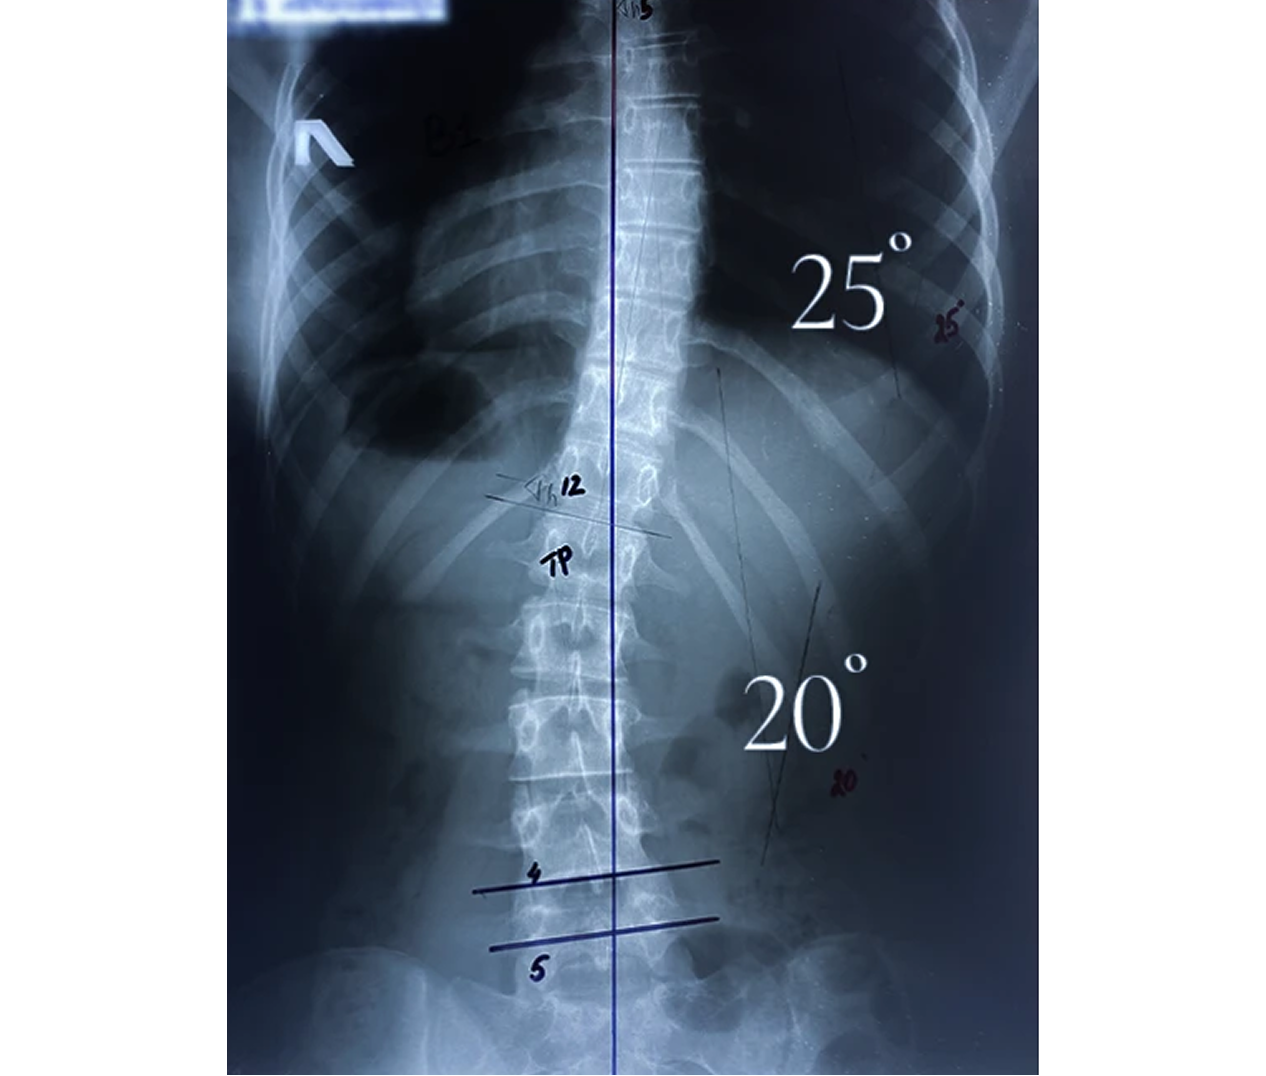

Корсет Шено — это «золотой стандарт» в лечении сколиоза у детей и подростков. В клинике Ортотис Центральная Азия в Алматы мы изготавливаем активные ортопедические корсеты, которые не просто удерживают позвоночник, а эффективно исправляют деформацию.

• Идиопатический сколиоз с углом искривления от 20° по Коббу;